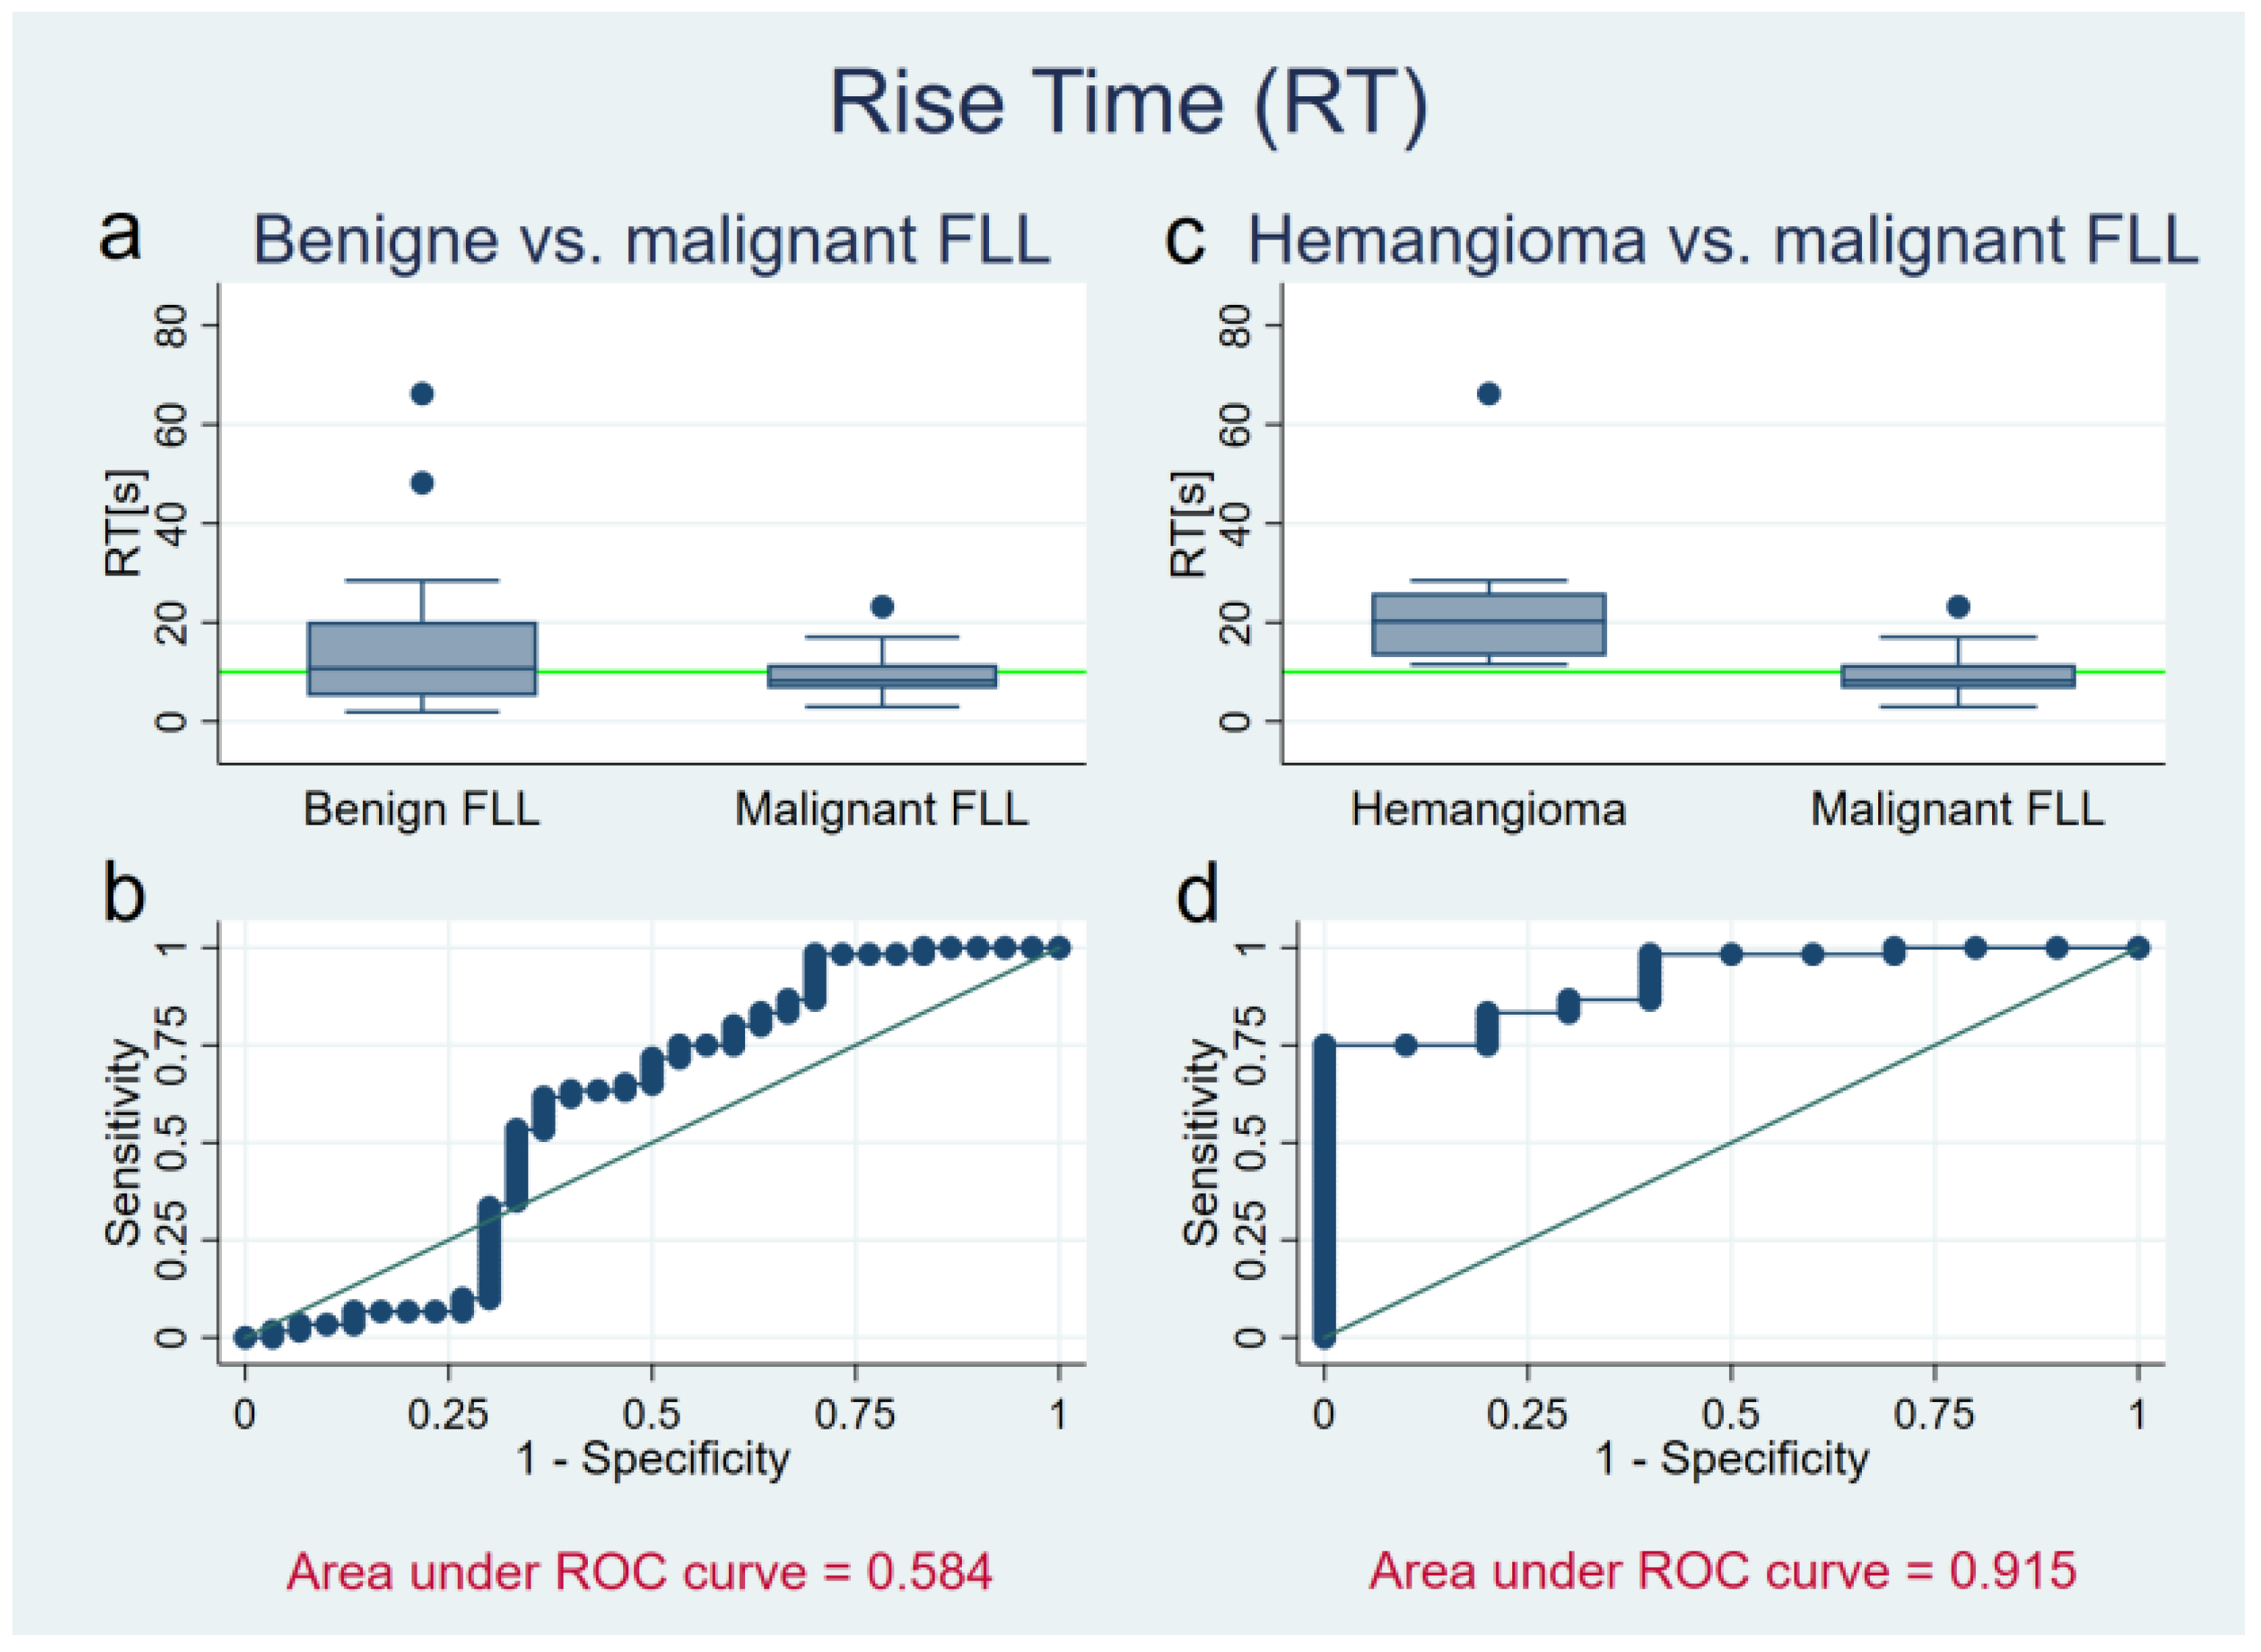

3.3. Rise Time